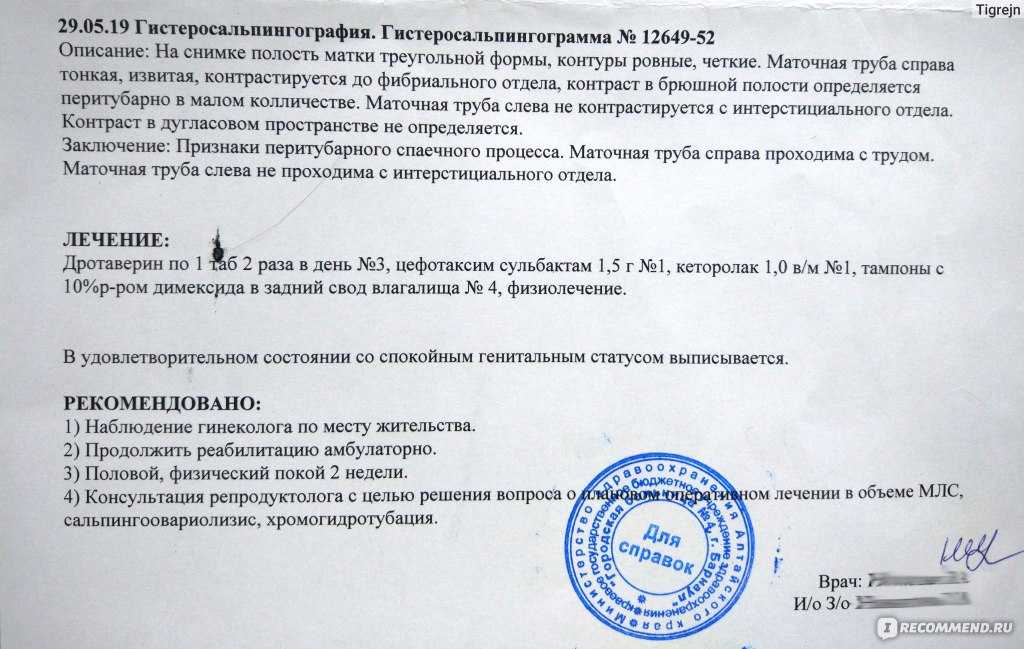

Медицинские снимки: Проходимость маточных труб

.jpg)

Раздел: Кадры-подсказки